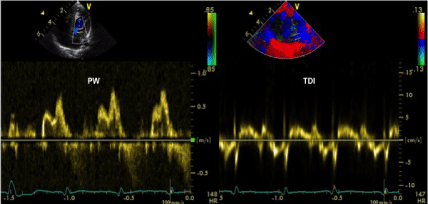

In April 2006, an apparently healthy male newborn was diagnosed to have signs of biventricular hypertrophy and sporadic ventricular premature beats of two morphologies, originating from the left ventricular apex and the RVOT. No foetal echocardiographic evaluation was accomplished at that time. The echocardiographic evaluation performed shortly after birth showed numerous large “echodense” masses localized intramurally in the left and right ventricle, compatible with multiple rhabdomyomas. The cavity was completely obliterated by three large masses localized at the left ventricular apex (Figure 1). Left and right ventricular mid cavities were almost entirely occupied by other masses (Figure 2). A large mass caused a significant obstruction of the LVOT with an intraventricular gradient of 47 mmHg (Figure 3). Another lesion, detected in the RVOT very close to the pulmonary valve, was responsible for a mild flow acceleration without significant gradient (Figure 4). The mitral pattern at pulsed wave Doppler evaluation showed signs of impaired left ventricular diastolic function (Figure 5).

Figure 5. Anomalous mitral pattern at pulsed wave Doppler evaluation showing signs of impaired left ventricular diastolic function